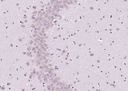

r氨基丁酸抗体

目录号:bs-2252R

商品规格:100ul